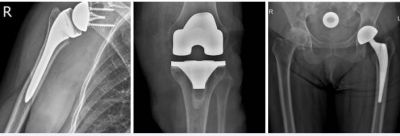

Големите стави – раменна, колянна и тазобедрена, поемат основната тежест при движение и са най-често засегнати от травматични и дегенеративни промени. „Смяната на става“ (ендопротезиране) е все по-чест избор за лекарите при тежки увреждания, причинени от заболявания като артроза, ревматоиден артрит, аваскуларна некроза, фрактури или след неуспешни предишни операции. Тези състояния водят до силна болка, ограничена подвижност и влошаване на качеството на живот. Медицинската практика вече е напреднала достатъчно, за да кажем, че ендопротезирането на големи стави е надежден, безопасен и доказано ефективен метод за връщане към активен начин на живот.

Като лекар, който има опит в оперативното лечение на големи стави чрез ендопротезиране, мога да потвърдя, че това е една от най-успешните и утвърдени ортопедични процедури в съвременната медицина. Тази хирургична интервенция цели замяна на увредена или разрушена става с изкуствена (ендопротеза), с цел облекчаване на болката, възстановяване на функционалността и подобряване качеството на живот на пациента.

Съществуват два основни вида протези:

Тотални (пълни) – подменят цялата става

Частични – заменят само увредения компонент на ставата

Използваните материали са биосъвместими и с висока издръжливост – метални сплави, керамика и медицински полиетилен. Изборът на протеза се извършва индивидуално, спрямо възрастта, състоянието и начина на живот на пациента.